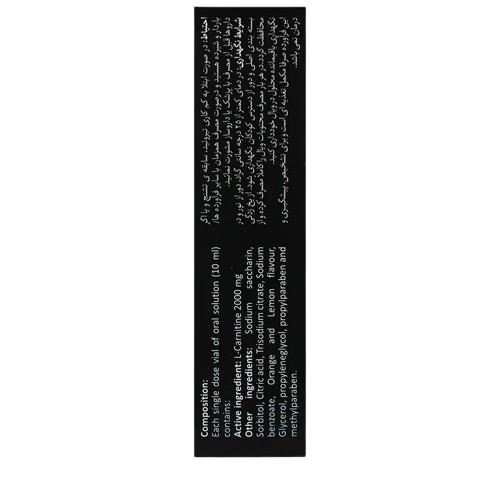

ترکیبات

هر ویال ۱۰ میلیلیتری از این محلول شامل:

- الکارنیتین: ۲ گرم، ماده اصلی برای تقویت انرژی و بهبود عملکرد عضلانی

- سدیم ساخارین: ۱۰ میلیگرم، به عنوان شیرینکننده

- طعمدهنده پرتقال: برای خوشطعم کردن محلول